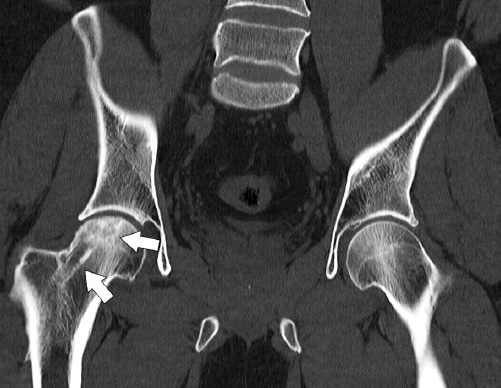

The changes in CT scans were correlated with the results obtained by X-ray examination at the corresponding follow-up periods. An important substrate of the pathological process, which we verified using CT, was the process of cystic foci formation in the femoral head, which is typical for the ANFH development and indicates its progression. These changes were absent in patients of both groups at 6 months. However, when analyzing the CT scans performed 12 months after operation, we observed an increase in the number of cyst-like lucencies in two patients of the control group, and in one of them the formation of destructive-dystrophic cysts was determined in the area of the acetabular roof.

A typical CT picture in patients of the main group included visualization of a bone canal in the metaepiphysis and bone autograft remodeling at a certain stage (Fig. 11).

Fig. 11. CT scans of the hip joints 12 months after the closed combined autografting of the left femoral head: contours of the bone canal and completed remodeling of the femoral head autograft (indicated by arrows) with preservation of its anatomical shape are observed